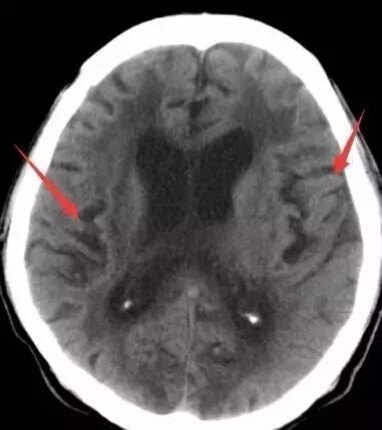

第一招:额角角度

脑萎缩~钝角

脑积水~锐角

第三招:脑沟和脑池脑萎缩-脑沟、脑池宽 脑梗塞——脑沟、脑池可见

脑积水——脑沟、脑池闭塞